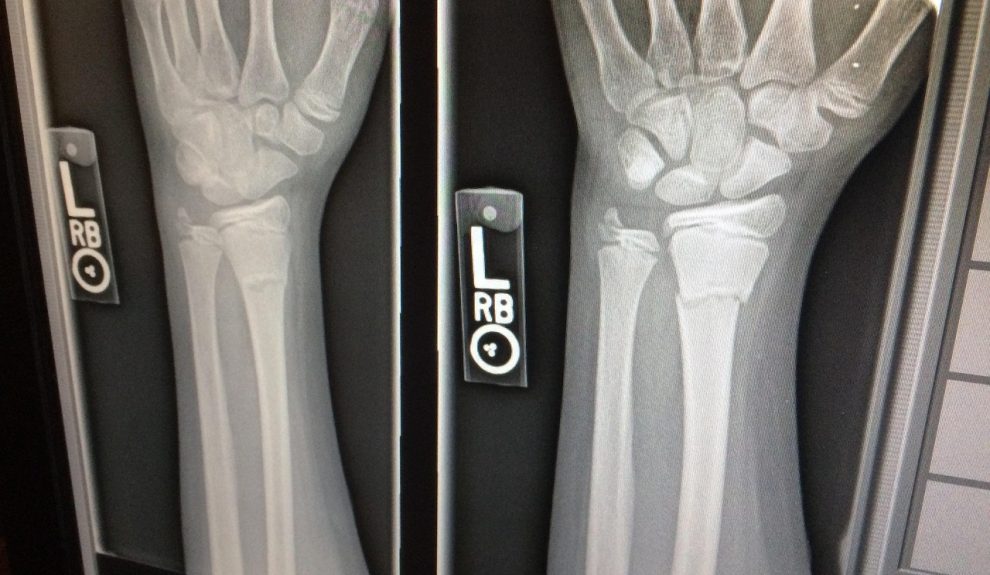

Cómo se analizan los huesos

Las tesis se basan en radiografías procedentes de centros como el Hospital Universitario de Canarias y el Hospital Universitario Nuestra Señora de Candelaria, junto al Instituto de Medicina Legal de Santa Cruz de Tenerife.

El equipo evalúa dos aspectos: la precisión —si distintos especialistas obtienen el mismo resultado al leer una imagen— y la exactitud —si esa lectura refleja la edad real del menor—. También incorporan inteligencia artificial para comparar miles de radiografías y mejorar el análisis: «Independientemente de quién evalúe la radiografía, la concordancia es muy alta»